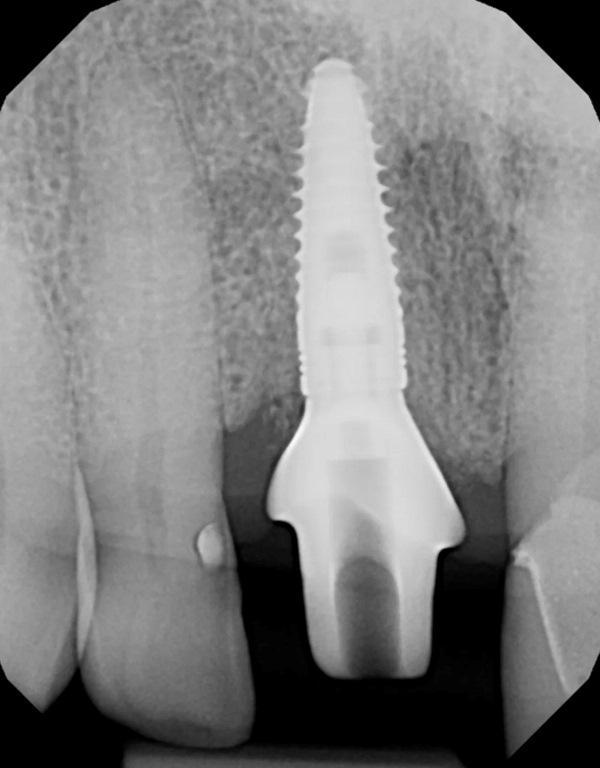

Для оценки сохранности корня на уровне десны и состояния окружающих тканей выполнена прицельная рентгенограмма зуба 1.1 (Фото 2, слева); для оценки зубных рядов выполнена панорамная реконструкция конусно-лучевой компьютерной томографии (КЛКТ) (Фото 2, справа). Проведено пародонтологическое обследование; остальная зубочелюстная система без патологических изменений. По зубу 1.1 отмечалась небольшая утрата кости с дистальной стороны, рентгенологических признаков периапикальной патологии не выявлено. Апикальнее корня зуба № 8, а также медиально и дистально от него имелась достаточная костная ткань для установки имплантата.

Фото 2. Прицельная рентгенограмма (слева) и панорамная проекция КЛКТ (справа), демонстрирующие перелом центрального резца и его взаиморасположение с окружающими структурами.

Выполнена прицельная рентгенограмма для проверки посадки формирователя десны и документирования позиции имплантата относительно анатомических структур (Фото 6). Для содействия формированию сгустка между мягкими тканями и «липкой костью» на десну наложено давление. Наложены швы 4-0 из кетгута для удержания мягких тканей в контакте с индивидуальным формирователем десны. В полости рта установлен временный ретейнер Essix; пациенту предписано носить его круглосуточно, снимая только для проведения гигиены, до следующего приема через 2 недели (Фото 7).

Фото 6. Прицельная рентгенограмма после установки индивидуального формирователя десны и гребневой костной пластики; документирована позиция имплантата относительно окружающих структур и глубина его расположения от уровня гребня.